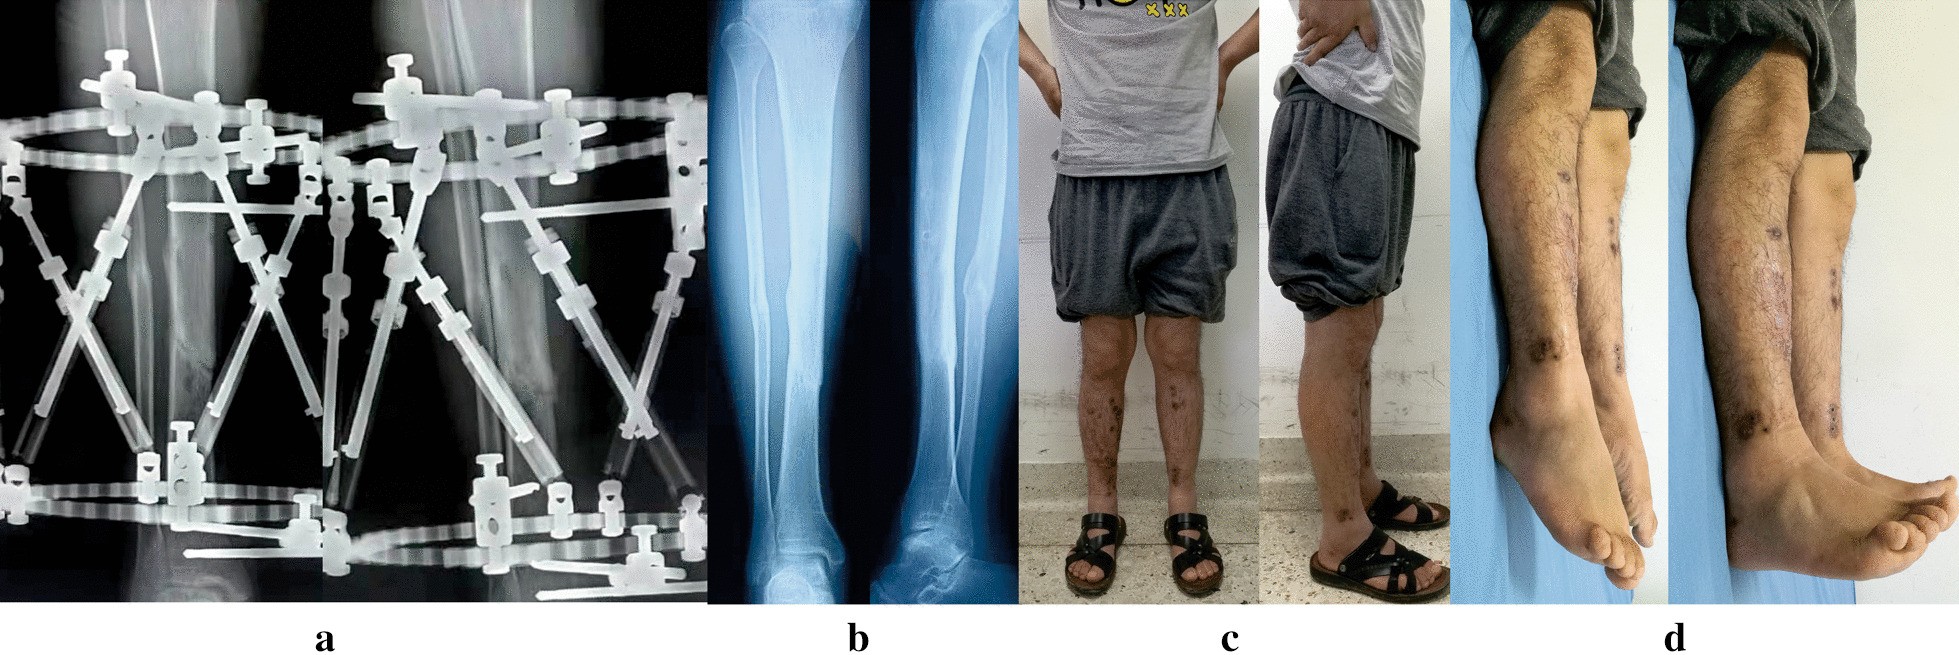

Fig. 4

Images of the same patient shown in Fig. 3. a Radiographs after 6 months from TSF application, revealing hone healed. b Radiographs 6 months later after removal of TSF. c, d Clinical follow-up images, obtained at 13 months after TSF removal